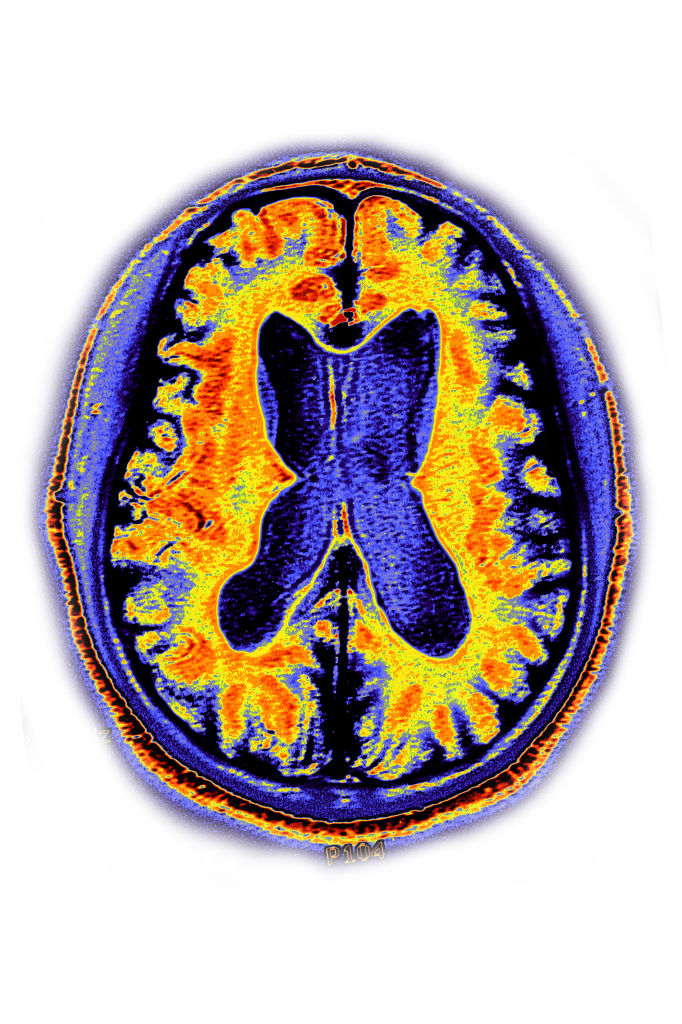

color-coded brain scan of alzheimer's, with yellow and red brain regions with atrophy shown in purple

Regions affected by Alzheimer's are shown in blue. It's unclear whether the FDA would require brain scans or behavioral and cognitive testing to show that a gene therapy works. (Image credit: BSIP/UIG/Getty Images)